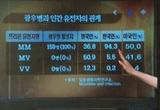

코돈129번 MM형의 문제

- 양기화 의학박사

한국인은 광우병에 잘 걸리는 체질이다?

- 양기화 의학박사